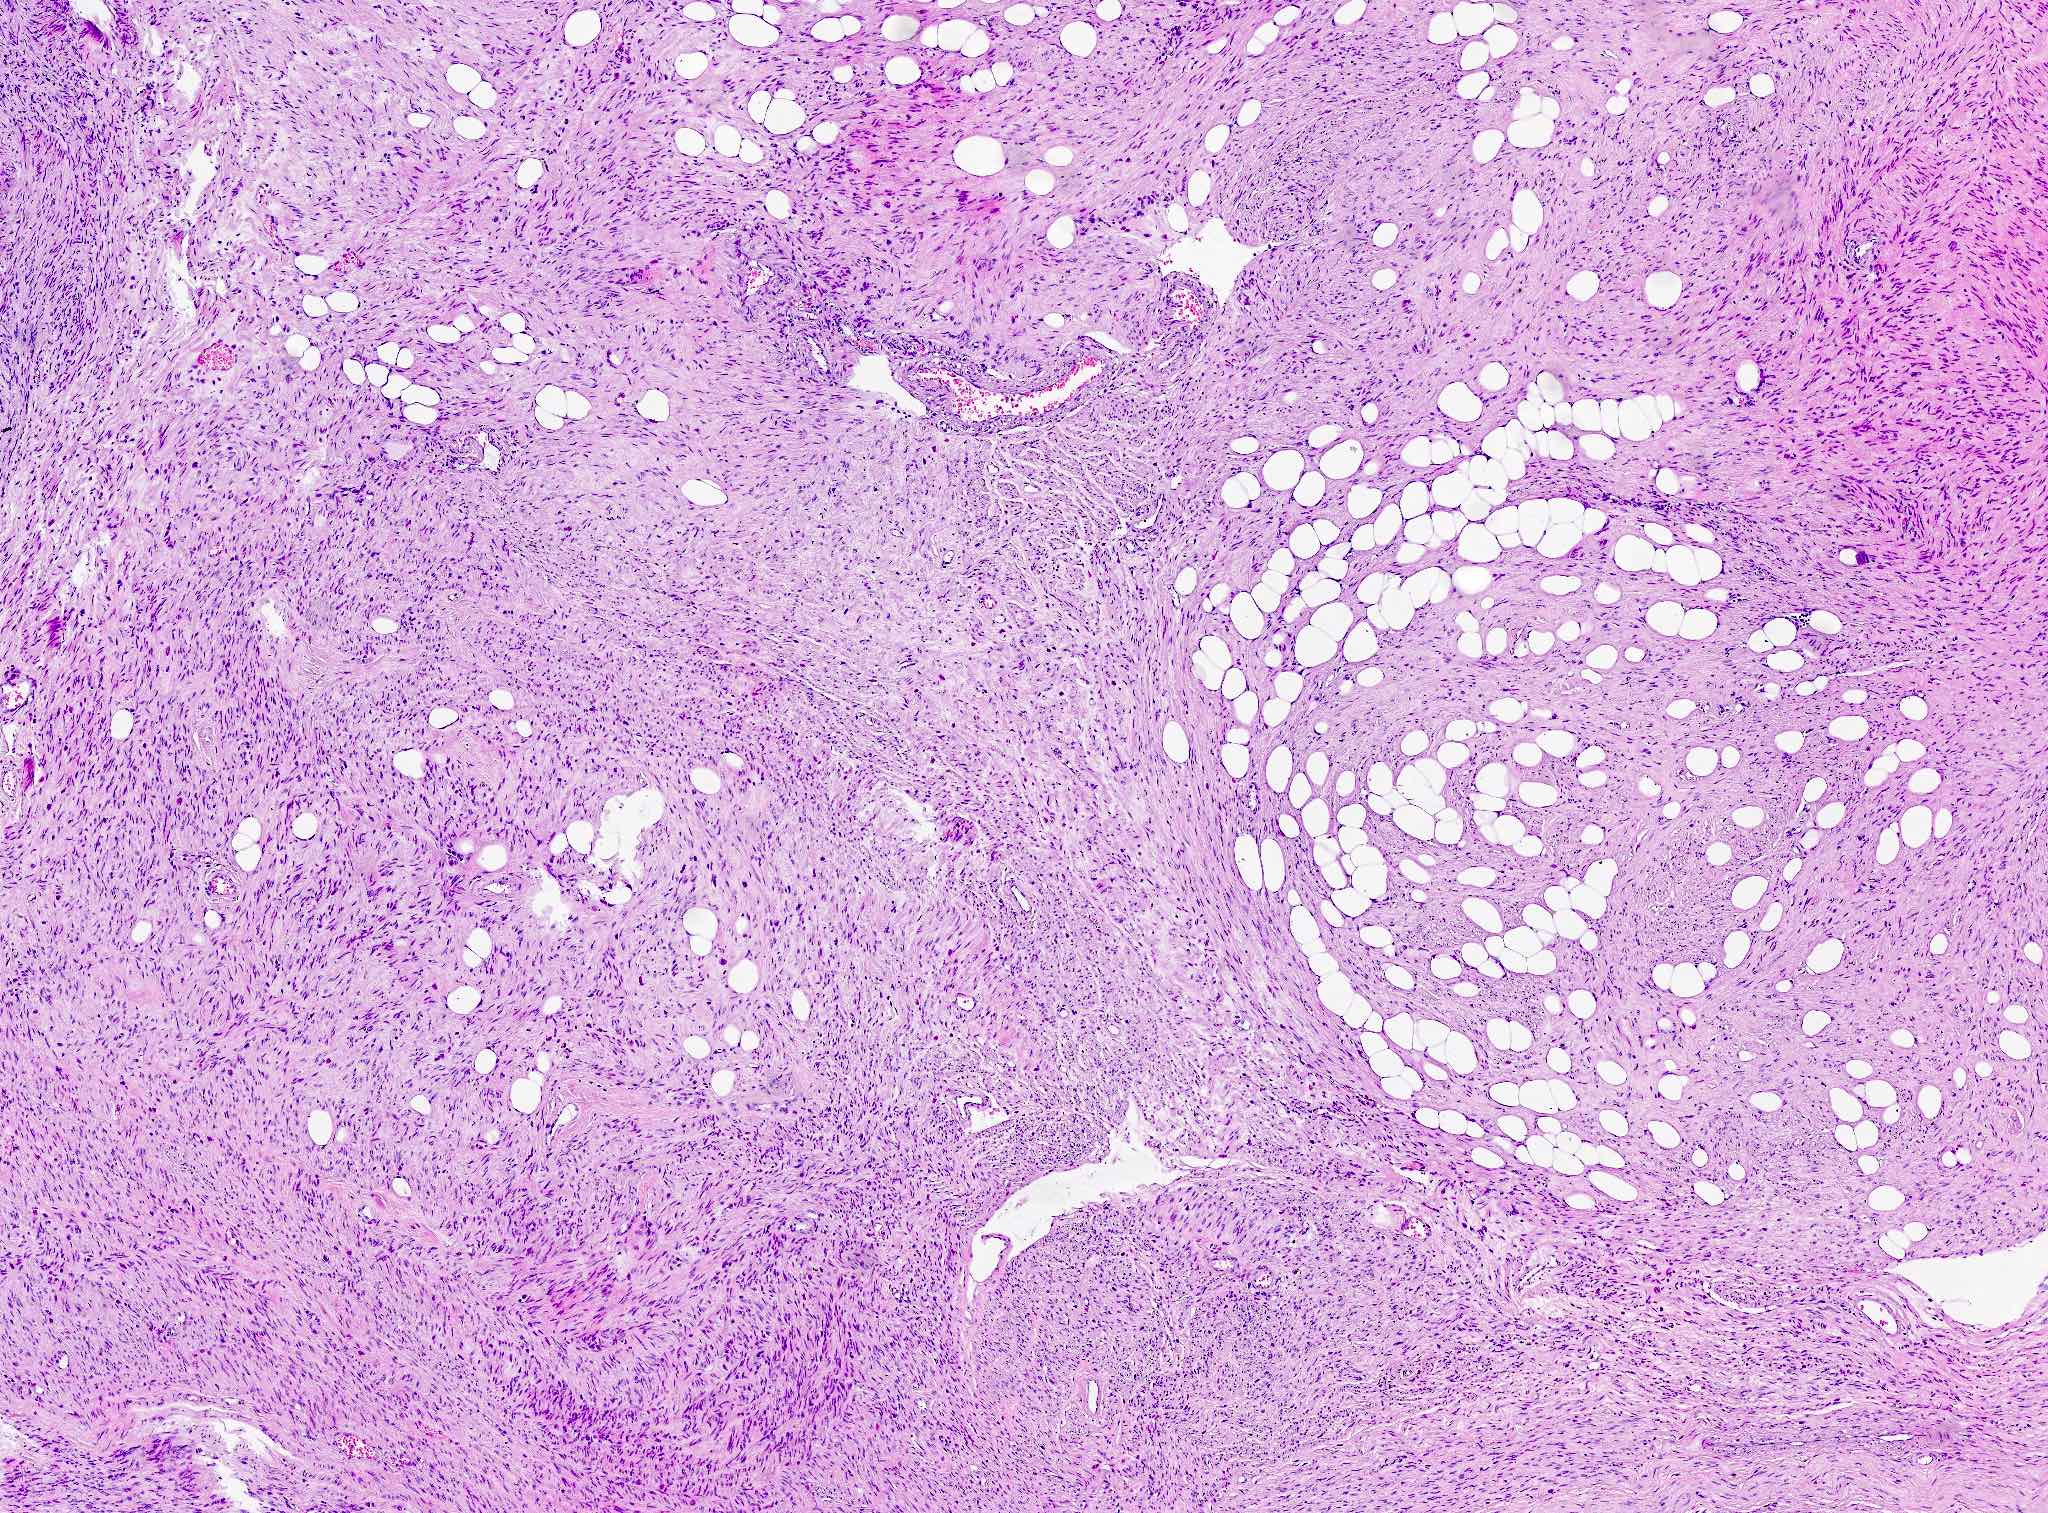

- Lipoleiomyoma:

- Tumor composed of smooth muscle cells mixed with mature adipocytes (variable quantity)

Microscopic (histologic) images

Contributed by Sabrina Croce, M.D., Ph.D., Kristina Doytcheva, M.D., Jennifer A. Bennett, M.D. (Case #508) and @Andrew_Fltv on Twitter